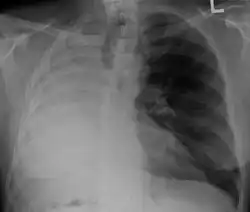

X-ray of a person who has had their right lung removed. Note how fluid has replaced the lung

After a pneumonectomy is performed, changes in the thoracic cavity occur to compensate for the altered anatomy. The remaining lung hyperinflates as well as shifting over along with the heart towards the now empty space. This space is full of air initially after surgery, but then it is absorbed, and fluid eventually takes its place.[9] The fluid which fills the residual space in the chest cavity slowly gelatinizes into a proteinaceous material, and the chest scaffold collapses slightly.